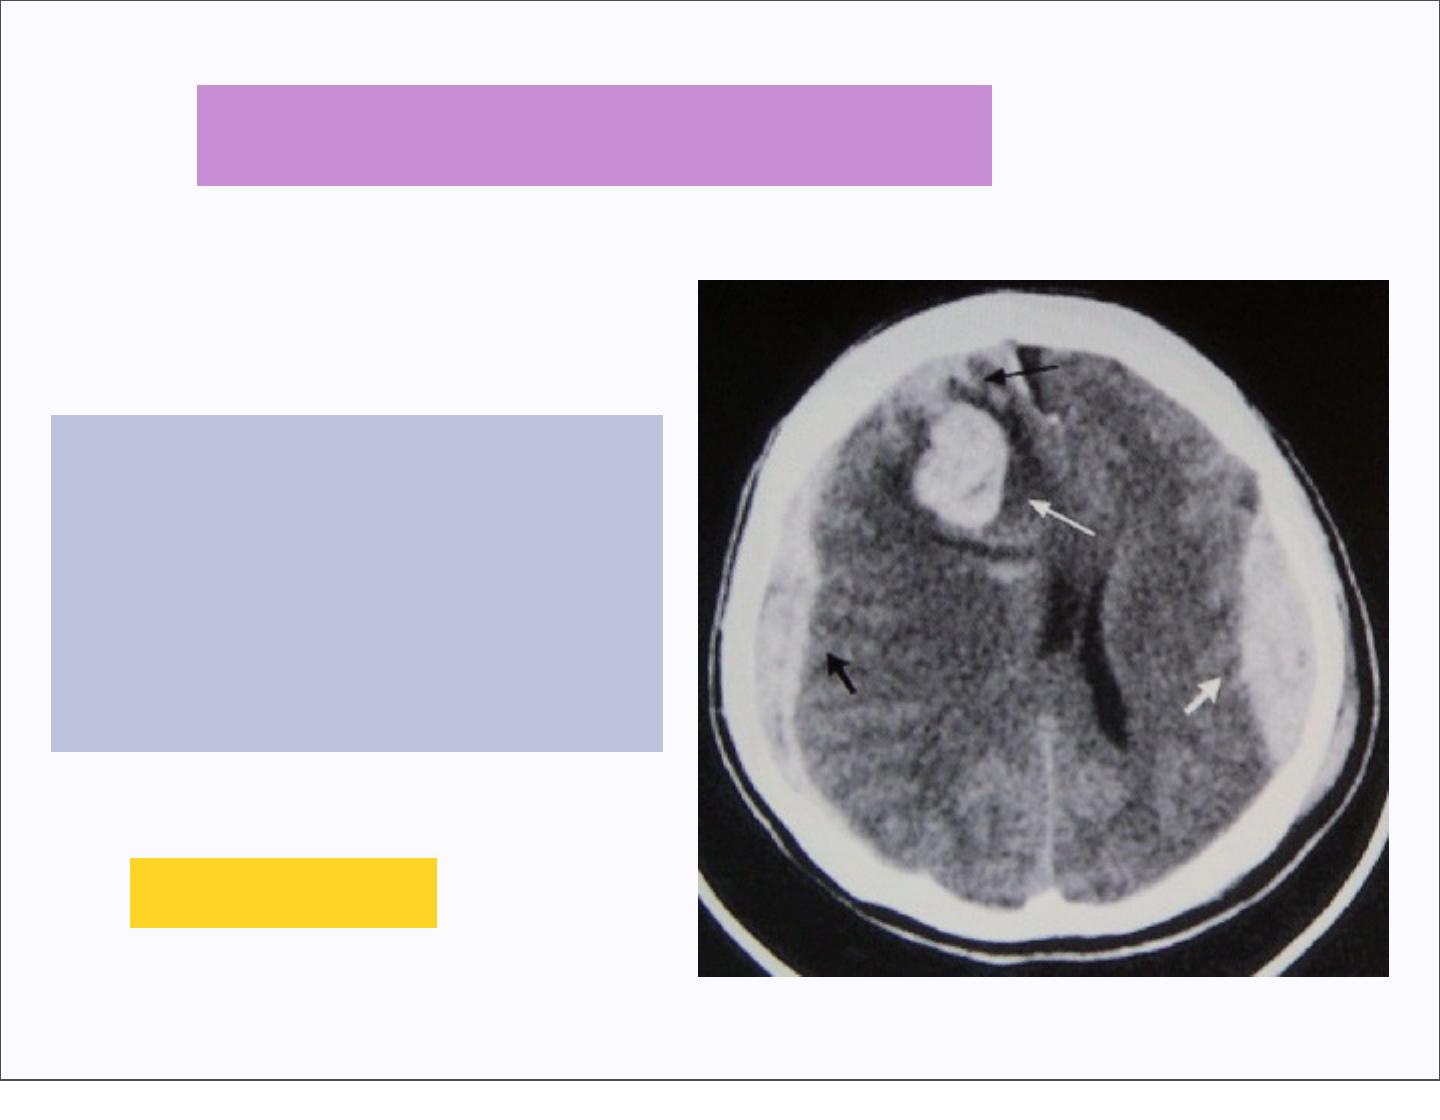

1.Lésions primaires

dues au traumatisme

= hématomes

= lésions axonales

diffuses